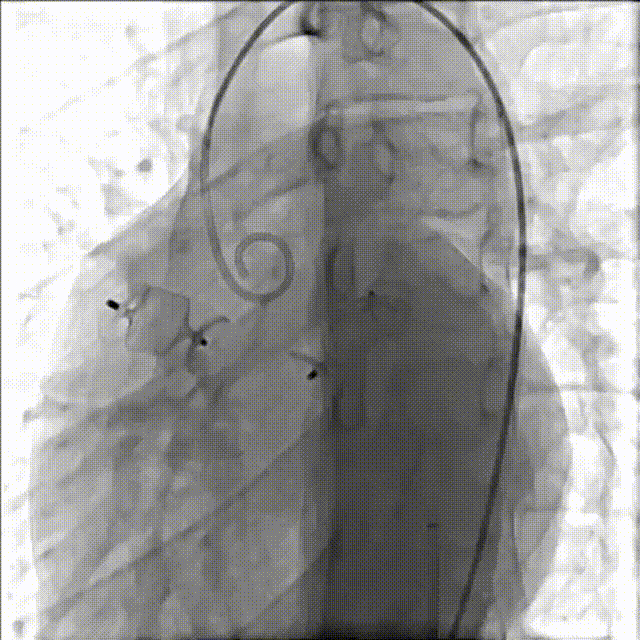

释放16mmAVP-II血管封堵器

术后造影提示封堵器位置良好

手术顺利,共计1小时10分钟,术中出血20ml,造影剂150ml,安全返回病房,心率56次/分,血压130/76mmHg